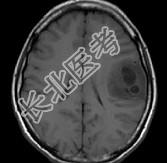

- 单项选择题女,33岁, 三个月前有右上肢及右颜面部麻木,伴耳鸣及头昏, 请根据所提供图像,诊断最有可能是 ( )

A、星形细胞瘤

B、脑血吸虫病

C、脑转移瘤

D、脑结核

E、脑脓肿